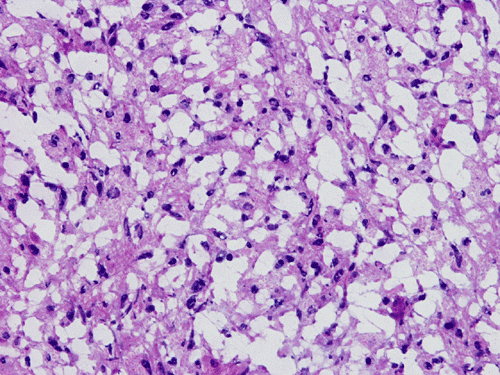

He was admitted again. In this admission, he developed left intraparenchymal hemorrhage associated with the enhancing mass, edema, and 0.4 cm left to right midline shift. A craniectomy was performed to evacuate the blood and biopsy the enhancing mass. The followings are representative images from the biopsy material.

Panel A to E are intra-operative cytologic preparation, Panel E to J are frozen section, Panel K to N are permanent sections.